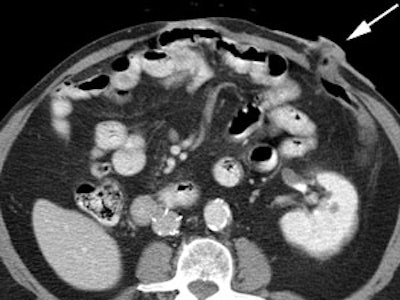

Bladder cancer: Dilute urinary activity in this patient's bladder allowed accurate detection of their bladder cancer (white arrows on CT, black arrows on PET scan). In general, urinary excretion of FDG limits evaluation of urinary tract malignancies, however, hydration and diuresis can improve diagnostic accuracy. |

|